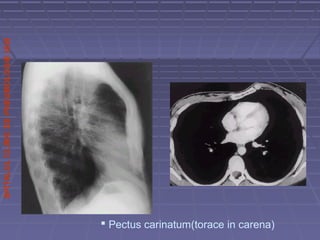

 Pectus carinatum(torace in carena)